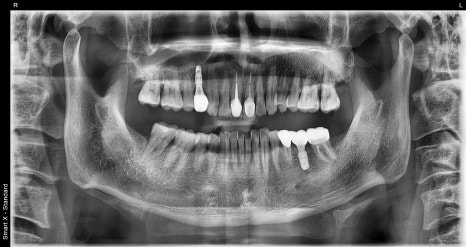

🖼️ 치료 후사진

왼쪽 사진: 신경치료와 임플란트, 보철 치료까지 모두 마친 후 촬영한 전체 파노라마 엑스레이입니다.

오른쪽 사진: 신경치료가 완료된 치아와 임플란트가 잘 자리잡은 모습을 보여주는 부분 엑스레이입니다.

➡ 신경치료가 끝난 치아는 뿌리까지 약재로 잘 채워졌고, 그 위에 보철물(크라운)도 잘 씌워졌습니다.

➡ 빠졌던 어금니도 임플란트로 기능이 회복되어, 환자분은 씹는 힘과 편안함 모두 만족하셨습니다.